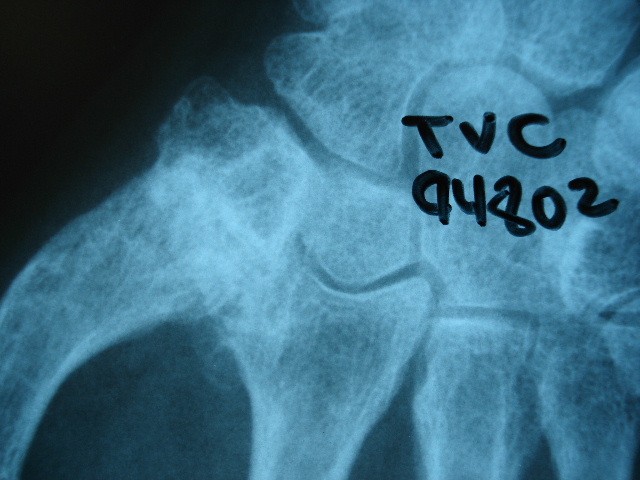

Fractura de cuello de fémur.

Fractura de cuello de fémur

Fractura de cuello de fémur con tornillos de tracción